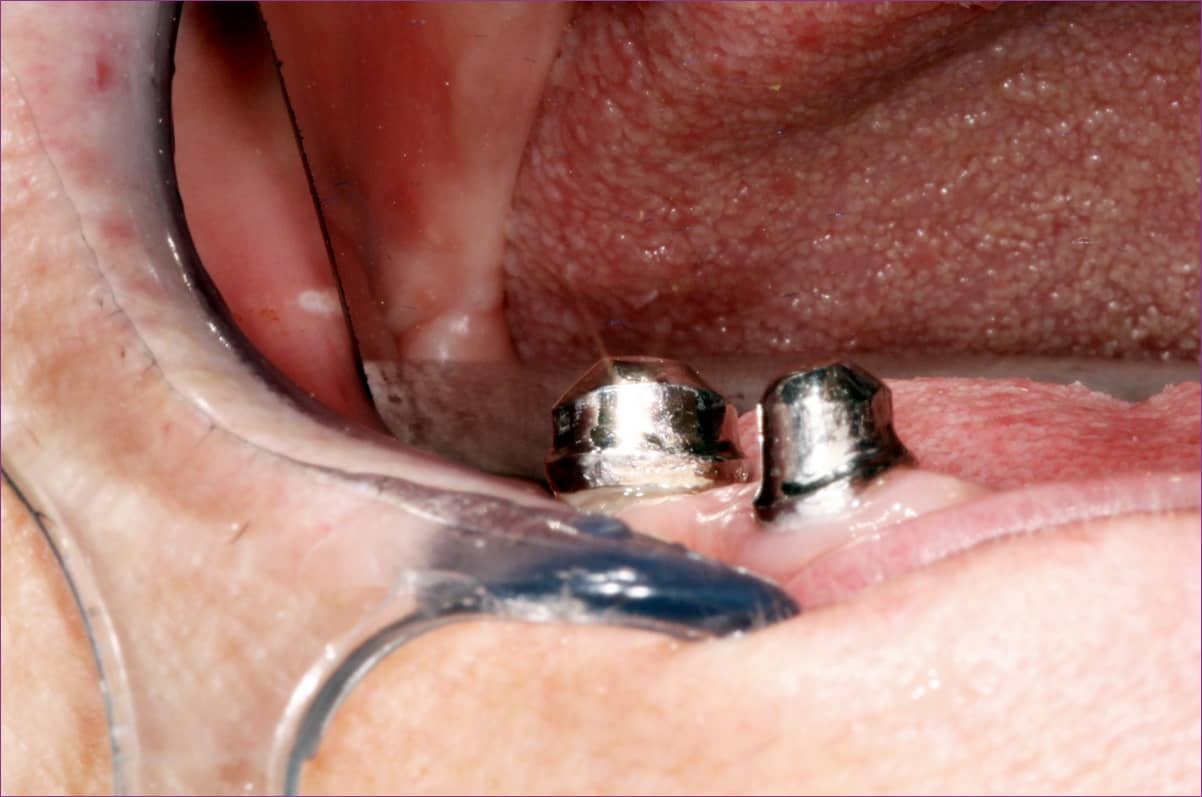

Az alsó állcsontra pedig cilindrokónuszos-teleszkóp elhorgonyzású fogpótlás lett a megoldás, az alábbi kép az SB5 primer teleszkópok beragasztása utáni állapotot mutatja.